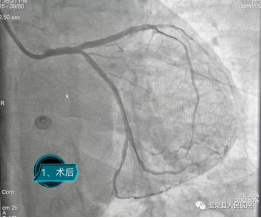

在咸宁市中心医院心血管内科李宾主任的指导帮扶下,温泉县人民医院介入诊疗中心团队开展心脏造影手术10台,其中PCI手术3台。并且成功开展我院首例冠状动脉左主干病变介入治疗,挽救了患者生命。冠状动脉左主干为整个心脏提供70%以上的血液供应,其急性闭塞意味着猝死的高风险,院外发病“九死一生”,又被称为“生命雷区”。此类手术在我院介入诊疗中心的顺利完成,标志着我院冠脉介入技术水平迈上新台阶,也将造福本区域更多的冠心病患者。